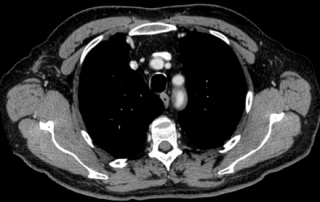

Scanner thorax abdomen pelvien : masse médiastinale antérieure et supérieure, absence d’atteinte du pédicule vasculaire, absence de nodule pulmonaire, scanner sous-diaphragmatique normal. Cible médiastinale taille 94 x 67 mm

TEP-FDG masse médiastinale hypermétabolique isolée